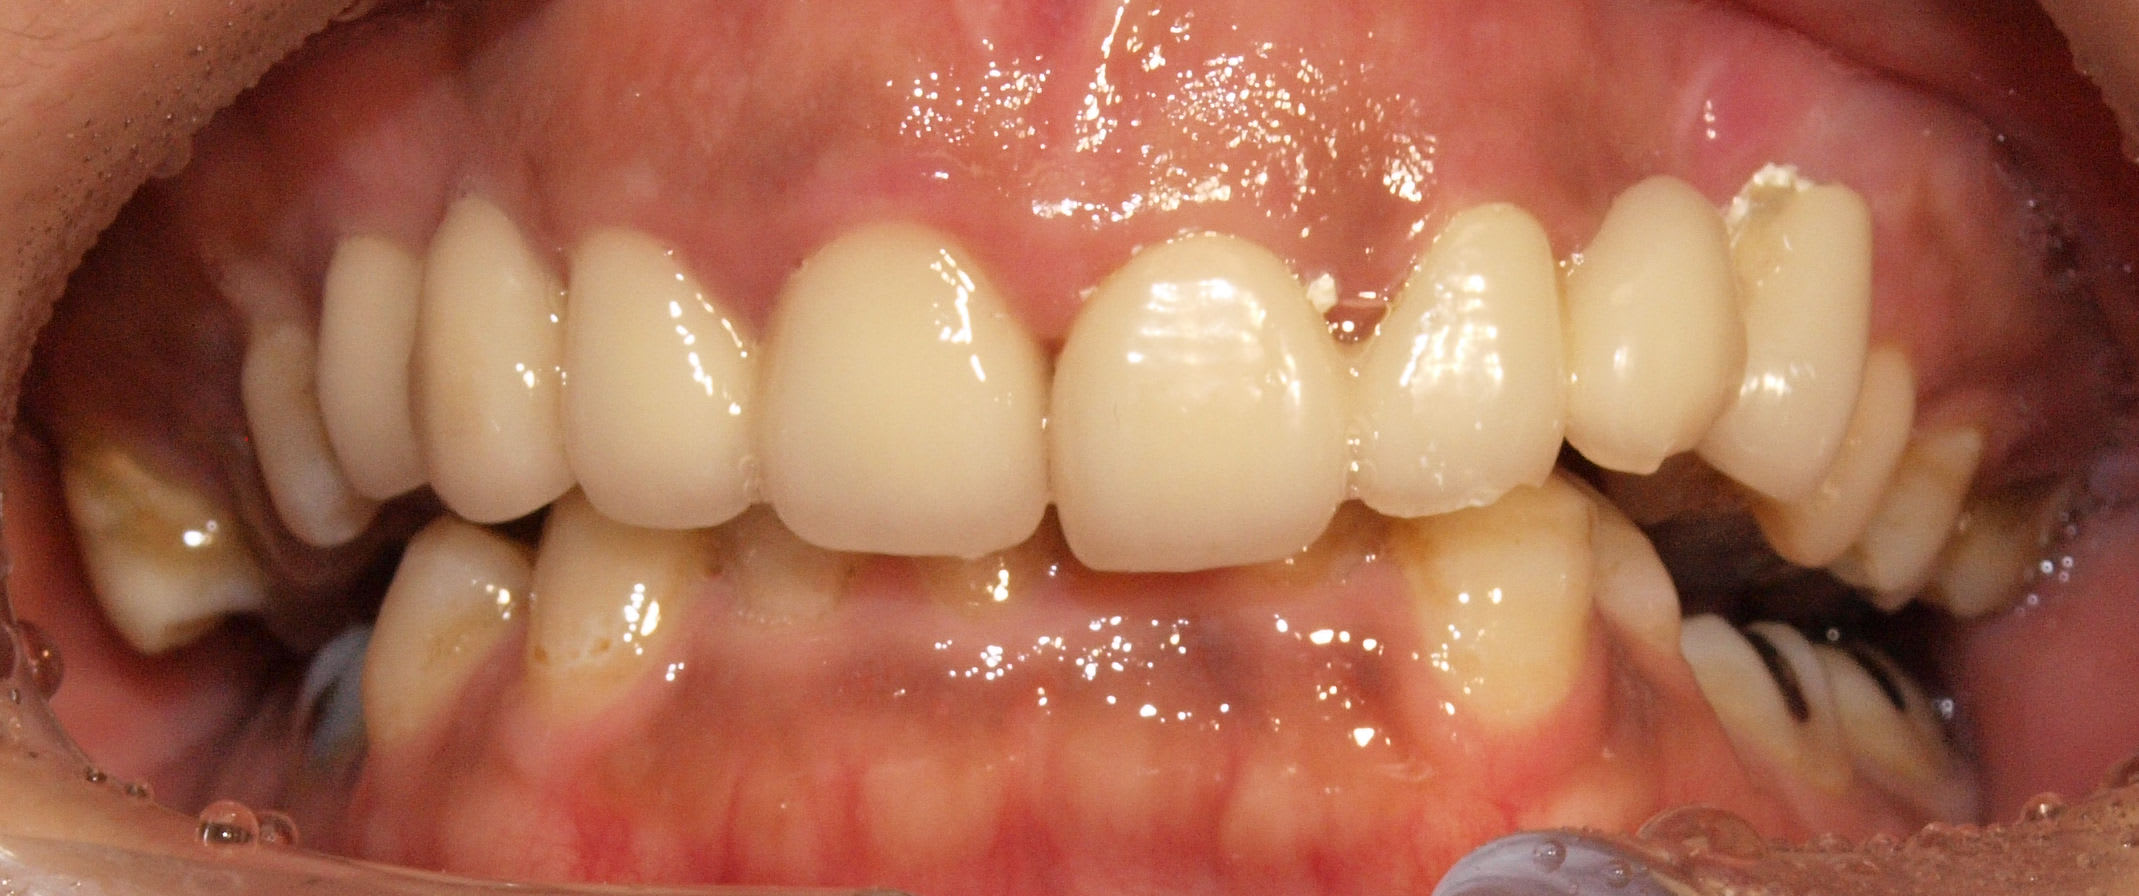

Patiente Japonaise avec bridge 21-24 qui se balade comme ca depuis 3-4 ans.

J'ai juste temporise en recollant aux carboxylates.

La patiente est en overbite severe.

Occlusion masquant totalement les incisives mandibulaires

P1273386 nic6im - Eugenol